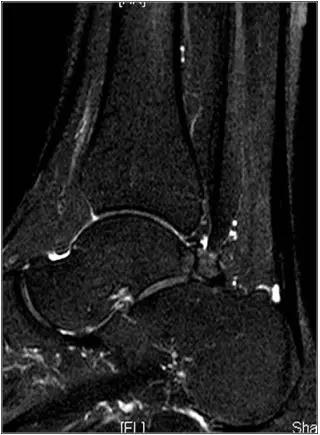

- 影像学表现为距骨后三角骨的存在或损伤以及距骨后突骨赘形成,导致踝关节跖屈受限,可伴随拇长屈肌肌腱鞘炎症及邻近滑膜不同程度的炎性增生 。

正常后踝韧带;MRI 冠状位T2-FLAIR示踝间后韧带(长箭)

男,11岁,自述后踝下方疼痛,活动时为甚,并有一突起。

- MRI 检查示距后三角骨及周围软组织有水肿信号,距后三角骨和距骨之间正常的低信号纤维连接中断,出现液性信号。

- 三角籽骨或距骨后三角结构模糊和变形,T1WI信号降低, T2WI信号升高,

- 周围脂肪水肿,

- 踇趾长屈肌腱信号升高,见鞘膜积液,